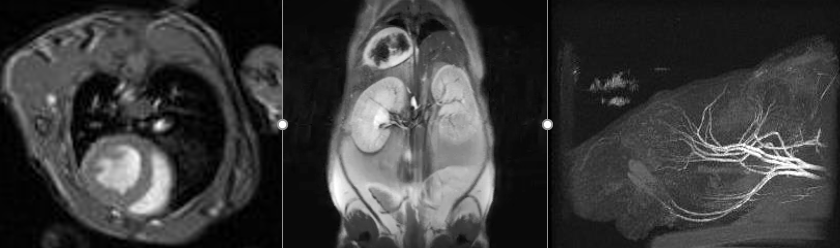

7.0T MRI

Bruker Biospin 7T PharmaScan

- T1 and T2 weighted scans for Anatomic Imaging

- Angiography

- Cardiovascular Imaging